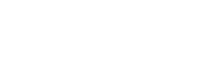

Resorbed Ridge Treatment Before

Resorbed Ridge Treatment Before Resorbed Ridge Treatment After

- thin ridge

thin ridge Pre surgical ct scan showed severely resorbed jaw bone